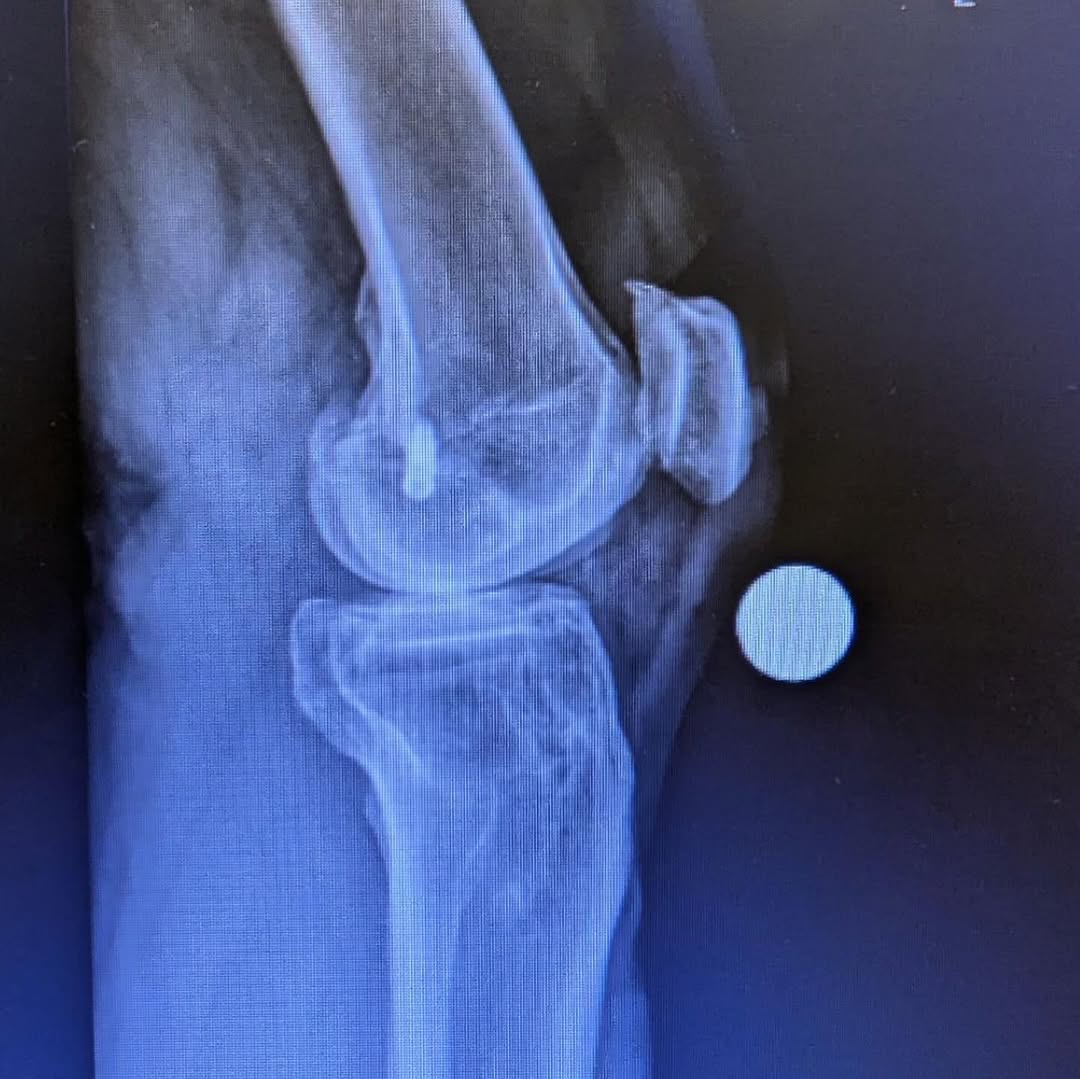

“How it was. And how it is…

I am 7 weeks post op on a Total Knee Replacement. My left knee was on its last leg, and I have been putting this surgery off for years. Post op X-Rays show everything is healing nicely. Many thanks to Dr. Nicholas Dirig, Derek Bobst, and their excellent team for my surgery. Thanks to Bill Wall of Physical Therapy Specialist for getting me back on track.